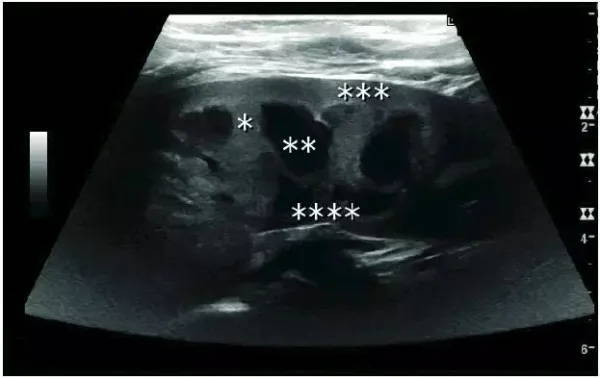

In patients with polycystic kidney disease, multiple cysts of varying sizes can be seen. In patients with advanced polycystic kidney disease, the kidneys are enlarged, with no obvious demarcation between cortex and medulla.

Advanced polycystic kidney disease with multiple renal cysts